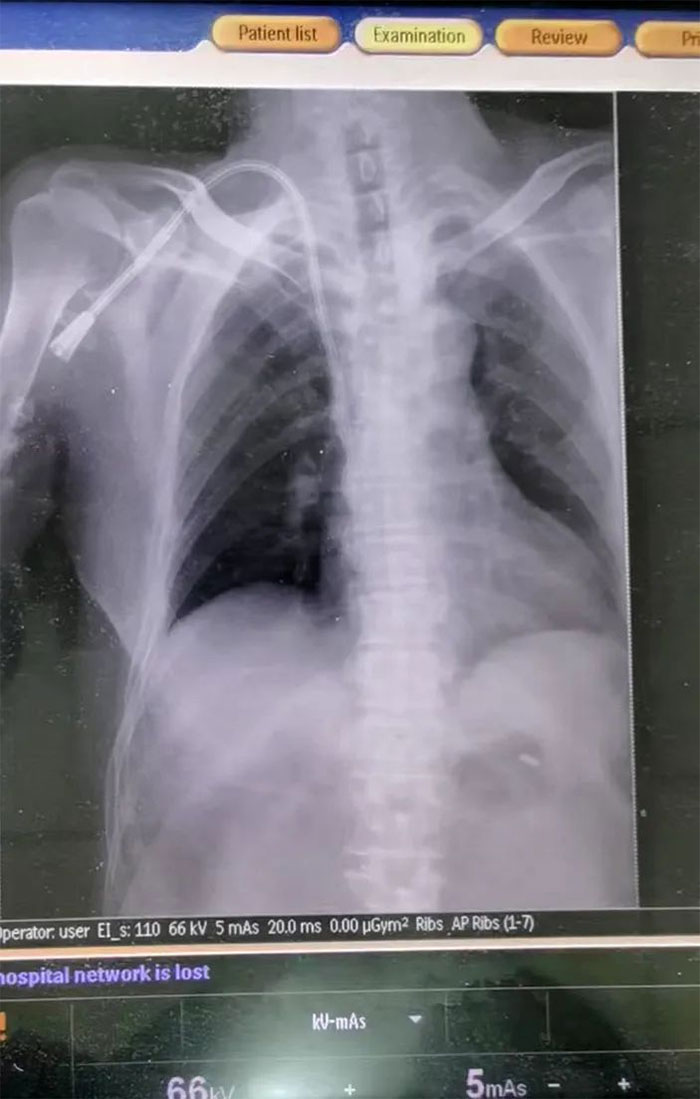

▲ DR驗(yàn)證,導(dǎo)管已經(jīng)到達(dá)指定部位

情況緊急,必須盡快為患者重新構(gòu)建一條長(zhǎng)期透析血管通路。為拯救患者,經(jīng)醫(yī)護(hù)團(tuán)隊(duì)反復(fù)討論,與患者家屬充分溝通病情后,決定為患者行右鎖骨下靜脈長(zhǎng)期導(dǎo)管置入術(shù)。在張慶成主任、李向明醫(yī)生及醫(yī)護(hù)團(tuán)隊(duì)通力協(xié)作下,最終成功為該患者建立“生命通道”,架起生命橋梁。再經(jīng)過DR驗(yàn)證,導(dǎo)管已經(jīng)到達(dá)指定部位,未出現(xiàn)出血等相關(guān)并發(fā)癥及靜脈阻塞癥狀,術(shù)后導(dǎo)管引血通暢,血液透析、輸血順利進(jìn)行。